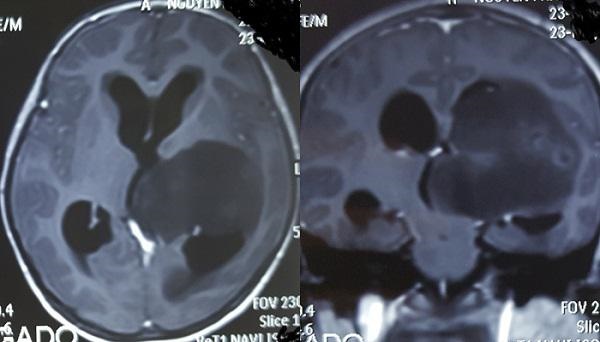

Hình ảnh khối u trong não bệnh nhi trước khi phẫu thuật.